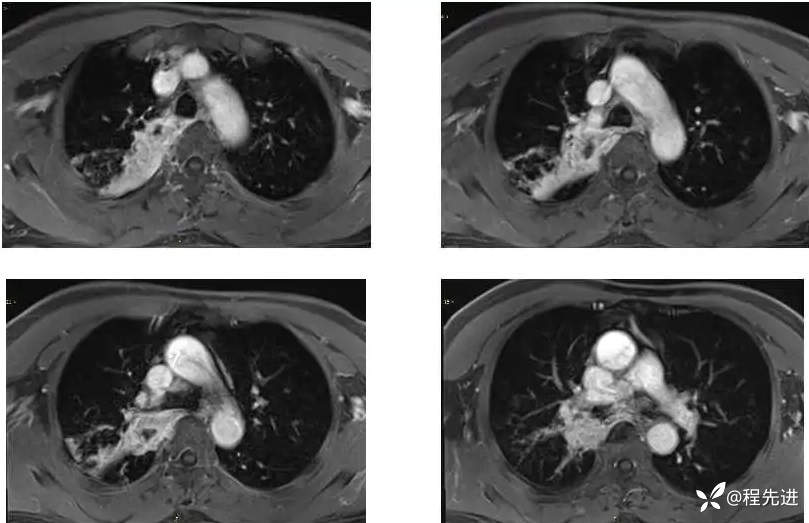

T1增强;

DWI 、ADC :